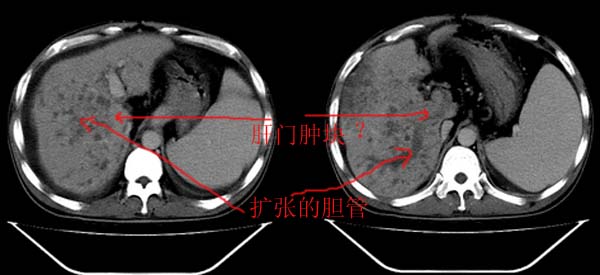

以下是引用yz在2006-6-2 12:20:00的发言:[br]肝左右叶比例失调,左叶体积明显缩小,肝边缘凹凸不平呈波浪状外观,肝左右叶可见不规则之斑片状低密度影,边界不清,以右叶为甚,肝门区增宽,增强后于动脉期病灶不均匀强化,门脉及延迟期均呈低密度,门脉主干及其右支无强化,以门脉右支明显,其内可见低密度影充填,门脉主干周围可见强化的细小侧支循环血管影。脾大,脾门血管明显增粗,脾后左侧膈脚前可见串珠状增粗强化血管影,并见胸腹水征。[br]1、考虑为弥漫性肝癌并肝门静脉主干及其右支癌栓形成,门脉海绵化。[br]2、肝硬化,脾大并门脉高压。[br]3、双侧少量胸水、腹水。